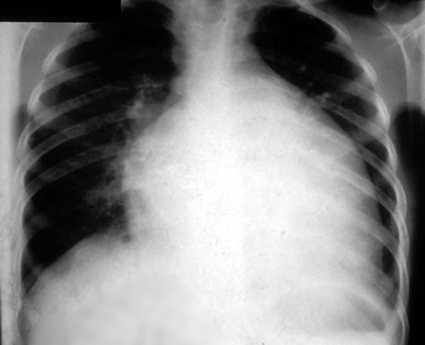

1) Hemolysis, which is episodic ("paroxysmal"). The degree of hemolysis depends on how many RBCs are abnormal. Unclear why it is sometimes nocturnal, as shown above. Chronic hemolysis can cause severe anemia, and renal failure from myoglobin-induced tubular damage